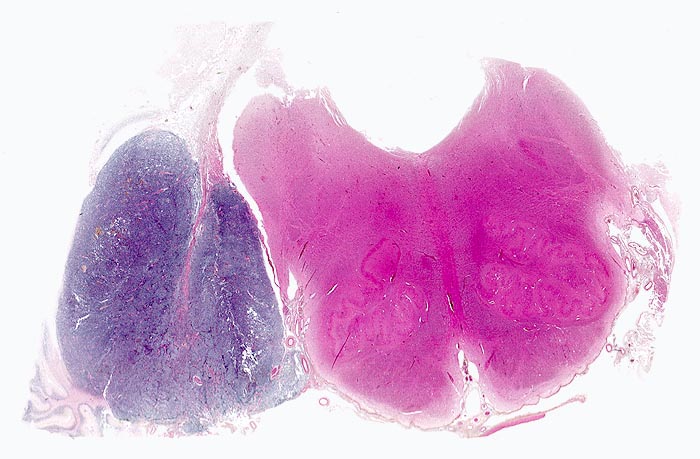

Die Makroskopie ist variabel. Meist sind Medulloblastome unscharf begrenzt, grau und weich, gelegentlich aber auch scharf begrenzt und derb.

• Scharf begrenzter rundlicher sehr zellreicher (deshalb blauer) Tumor.

Pathologischer Befund

Normalbefund